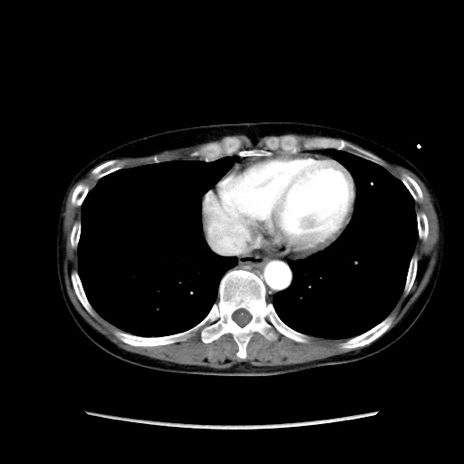

症例32(横断像)

【症例】40歳代 女性

【主訴】上腹部痛、嘔気・嘔吐

【現病歴】約9時間前頃から急に上腹部痛、嘔気、嘔吐が出現。改善しないため救急要請。

【既往歴】子宮頚癌(広汎子宮全摘術、放射線療法)、腸閉塞

【身体所見】腹部:平坦、軟、腸雑音亢進、上腹部を中心に腹部全体に圧痛あり。

【データ】WBC 8400、CRP 0.03